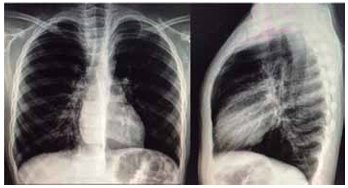

(Arquivo pessoal; imagens usadas com autorização)

Em relação à conduta, assinale a alternativa mais correta.